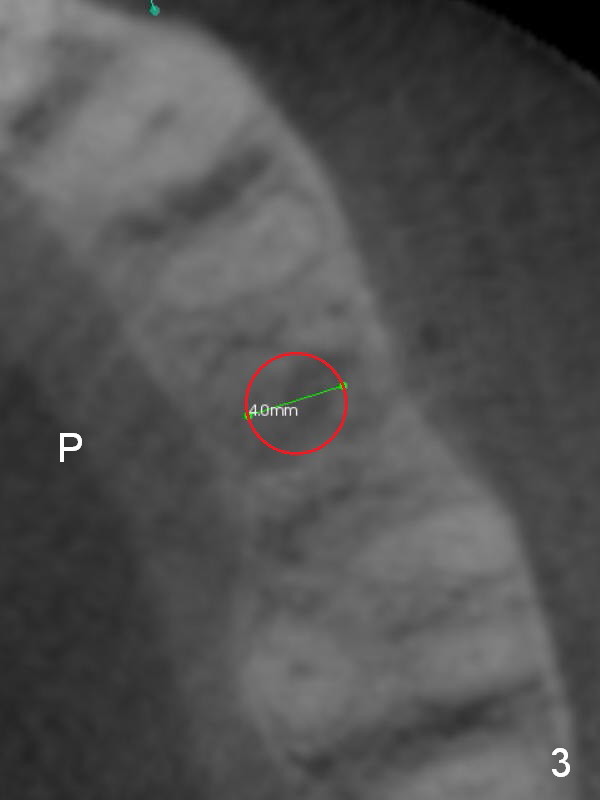

A 74-year-old man has diabetes. Implant osteointegration appears to be slow at #4, while the implant at #28 failed once. He requests implant at #13 (Fig.1). It seems that the bone is wide enough (8 mm, Fig.2 (CT coronal section) (P: palatal)) to hold a 4 mm implant (Fig.3 (axial section)). Since bone density is low at the coronal (100-200 units) and middle (50-100 units) segments (Fig.2), bone condensation will be beneficial. To facilitate wound healing, flapless approach is adopted using 1.6 mm pilot drill (Fig.4), followed by 1.4/2.6 mm bone expander. In fact there is resistance to expansion in the zone 1. Magic expander (3.0 mm) is also tried with difficulty. It appears that bone density is higher than expected. The second portion of Magic Surgical Kit is then used: 3.3 mm Magic Drill for 15 mm (gingival level, followed by Final Drill). A 4x13 mm IBS implant is seated incompletely. The osteotomy is further enlarged by 3.8 mm Magic Drill for 11 mm and deepened with 3 mm drill until 18 mm. Finally the implant is placed at a satisfactory level with insertion torque > 50 Ncm (Fig.5). A 4.5x4(3) mm abutment is placed and periodontal dressing is applied. The patient chooses to return for impression 6 months postop (Fig.6). The abutment changes to a 4x4(4) mm one. The crown is recemented nearly 2 years post cementation, which is related to distal and deep placement of the implant and bruxism (Fig.7).